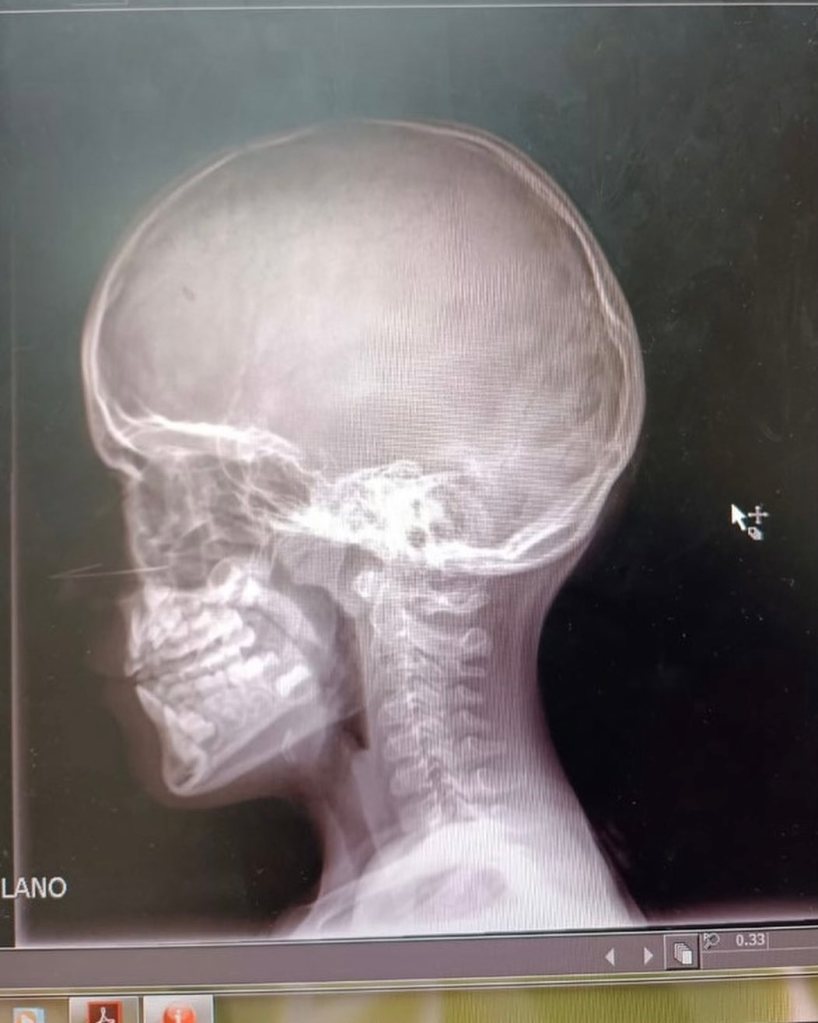

Acudí a urgencias, por posible trauma craneo encefálico, rayos x etc.

Gracias a Dios no hubo trauma, ni daño severo. A pesar que luego de haber vomitado el protocolo es de 24 horas bajo observación médica, atentos los síntomas alerta (volver q vomitar, dolor de cabeza fuerte, somnolencia excesiva)